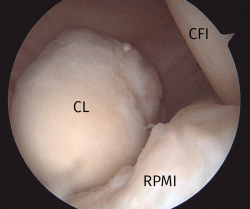

Figura 1. Imagen del compartimento posteromedial desde una visión transescotadura desde el portal anterolateral, rodilla derecha. Se evidencia la presencia de un cuerpo libre “oculto”. CFI: cóndilo femoral interno; CL: cuerpo libre; RPMI: rampa posterior de menisco interno.